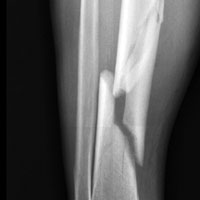

Исследуемая когорта состояла из 4972 человек в возрасте 20–85 лет. Распространенность экземы в выборке составила 7,4% (95% доверительный интервал (ДИ) 6,5–8,3), переломов разной локализации — 32,3% (95% ДИ 30,7–33,9), с преобладанием тазобедренных переломов и переломов позвоночника. В результате анализа ученые выявили, что наличие экземы в анамнезе ассоциировано со снижением МПКТ всей бедренной кости, в том числе ее вертела, а также поясничного отдела позвоночника, но не включая шейку бедра. Также специалистами установлена связь указанного заболевания кожи с остеопенией и остеопорозом вертела. У взрослых пациентов с хронической экземой риск перелома разной локализации превышал таковой лиц без этой кожной патологии (скорригированное отношение шансов (СОШ) 1,48; 95% ДИ 1,10–1,99; p=0,01). Пациенты с экземой имели повышение риска перелома бедра и позвоночника (СОШ 1,87; 95% ДИ 1,02–3,43; р=0,04). Развитие остеопороза ассоциировалось с ежедневным применением пероральных глюкокортикоидов ≥1 мес (СОШ 1,44; 95% ДИ 1,05–1,99; p=0,02).